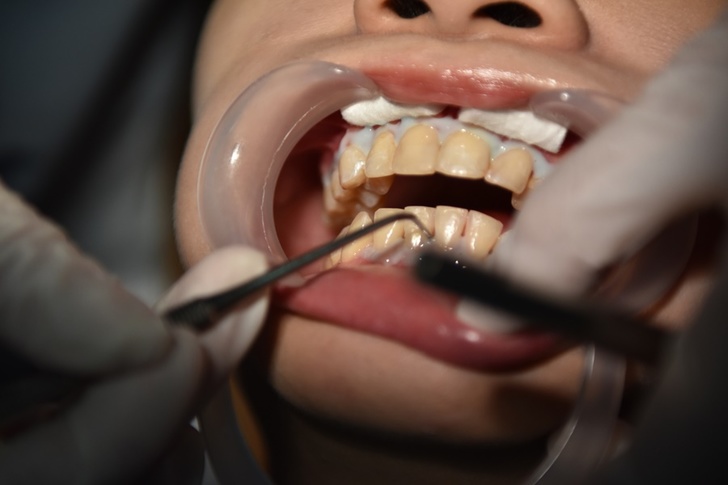

牙齒美白當天會進行清潔程序,

然後是色板對色、接著是牙齦保護程序以及塗抹美白藥劑後用冷光機照射每8 分鐘 一次,

首先要先進行清潔程序─洗牙,洗牙是這整套療程最不會讓下巴會酸的程序之一,

後面套上括口器要開始美白下巴絕對會痠到一個不行!

洗完牙齒後進入重頭戲~醫師再來要先塗抹牙齦保護劑徹底將牙齦與美白藥劑做一個隔絕,塗抹過程中院內撥放著輕音樂又躺在舒適診療椅上是非常放鬆地!